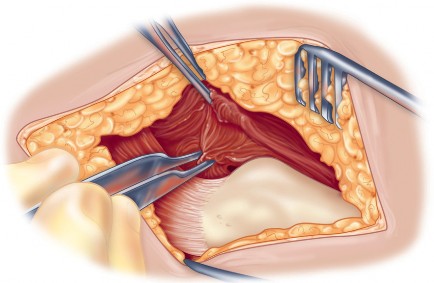

Optimizing Exposure with the Sharp Curved Hohmann

Once the anterior capsular exposure is achieved, a T-shaped or H-shaped capsulotomy is performed. The hip is then dislocated anteriorly with external rotation, extension, and adduction. After the femoral neck osteotomy is completed and the femoral head is removed, attention turns to acetabular preparation.

Acetabular exposure is the most technically demanding aspect of the lateral approach. To optimize exposure, the strategic placement of retractors is paramount. A sharp curved Hohmann retractor is carefully placed over the anterior lip of the acetabulum. The sharp tip must engage the bone securely to prevent slippage. This retractor serves a dual purpose: it retracts the anterior capsule and the elevated abductor-vastus flap anteriorly, providing unimpeded visualization of the anterior and superior acetabular rim.

Additional retractors are utilized to complete the exposure. A blunt Hohmann or Cobra retractor is placed inferiorly beneath the transverse acetabular ligament to retract the inferior capsule and soft tissues. A third retractor may be placed posteriorly. The precise placement of the anterior sharp curved Hohmann is the key to preventing the abductor mass from obscuring the surgeon's view during reaming and cup impaction.